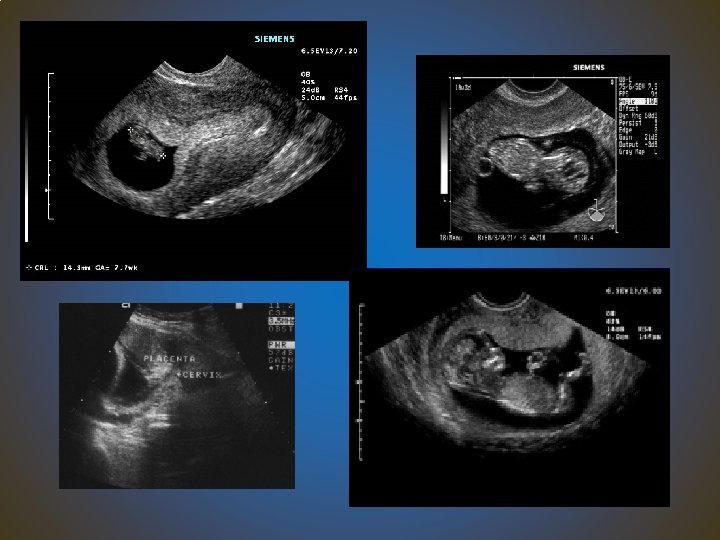

Basic: Early pregnancy (8 -12 weeks) ultrasound The aims: 1. become familiar with machine set up and use of the transabdominal probe (including probe orientation) 2. To gain competence in undertaking a basic ‘dating scan’ using TAS between 8 -12 weeks gestation 3. be aware of what can and cannot be seen using the transabdominal route in early pregnancy.

Basic: Early pregnancy (8 -12 weeks) ultrasound • Trainees are required to gain the TAS competences “under supervision” • gain exposure to, and experience in, use of the TV probe, but TVS competencies are not mandatory • maintain a formal log of on going ultrasound experience once basic competence has been confirmed. ( 3 OSATS per year at least to maintain competency)

Basic: Early pregnancy (8 -12 weeks) ultrasound learning outcomes • ultrasound identification of an intrauterine pregnancy • ultrasound identification of cardiac activity • basic first trimester biometry • referral as required • Be aware of own limitations and competencies • OSATS Trans-abdominal ultrasound examination of early (8 -12 week) pregnancy Completion of basic module form- sign off

Basic: Ultrasound assessment of fetal presentation (size), liquor and the placenta The aims of this module are: 1. become familiar with ideal machine set up and use of the transabdominal probe (including probe orientation) 2. gain basic competences that are potentially useful in day-to-day obstetric practice, including out of hours situations: i. e. lie, presentation, placental site and liquor assessment, assessment cardiac activity (Basic biometry techniques will be taught but competence to the level of ‘independent practice’ is not required)

Basic: Ultrasound assessment of fetal presentation (size), liquor and the placenta • ‘sign off’ is not the completion of training but a ‘springboard’ into experiential learning with maintenance and enhancement of the basic skills • maintain a formal log of on going ultrasound experience once basic competence has been confirmed. • i. e. produce evidence of continuing experience each year

Ultrasound assessment of fetal size, liquor and the placenta - Learning outcomes • basic ultrasound assessment of fetal lie/presentation ( including cardiac activity) • basic assessment of placental location • basic assessment of liquor volume • fetal size under supervision • referral as required

OSATS ( e-porfolio) Trainees should maintain an awareness of the limits of their own competencies OSATS: • 1. Fetal measurement, lie and presentation • 2. Liquor assessment (AFI and maximum pool depth) • 3. Placental assessment. • Completion of basic module form- sign off